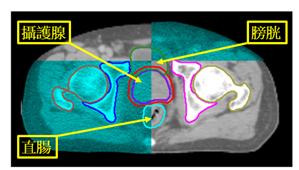

首先設計個人化之固定模具結合個人化腹部壓縮設備,進行4D電腦斷層攝影,必要時結合呼吸調控技術,進行治療前模擬。之後,將各式影像例如磁振照影、電腦斷層攝影與正子攝影等多種影像透過影像融合技術 ,精準定位出腫瘤位置 (圖二),同時醫師透過腫瘤靶區的圈選與透過人工智慧(Artificial Intelligence, AI)系統進行周遭正常組織之標定,與醫學物理師討論進行治療計畫設計,透過動態弧形技術給予腫瘤需的劑量、正常組織須限制的劑量,治療入射角度,治療入射方向等細節,來增加腫瘤精準治療包覆性與成功降低周遭正常組織劑量,來成功達到腫瘤消融與保護正常組織的目的。(圖三)

圖三、與醫學物理師討論進行治療計畫設計,包括腫瘤需給予的劑量、正常組織須限制的劑量,治療入射角度,治療入射方向等細節,來增加腫瘤精準治療包覆性與成功降低周遭正常組織劑量